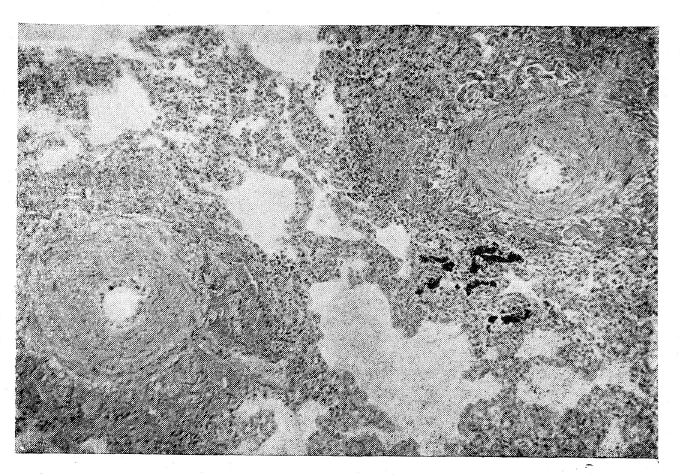

При гистологическом исследовании легочных артерий и их ветвей отмечено избыточное разрастание внутренней оболочки, как диффузное, так и в виде бляшек. Специальной окраской на жир в некоторых из них выявлено значительное скопление липоидов. В сосудах мышечного типа отмечена гипертрофия мышечно-эластического аппарата. В артериолах — нередко гиалиноз стенки. Стенка многих сосудов малого калибра имела зернистый или глыбчатый вид. Вокруг мелких сосудов отмечалось избыточное разрастание соединительной ткани (рис. 1).

Микрофотограмма легкого. Окраска гематоксилин-эозином. Малое увеличение — окуляр 7, объектив 6. Просветы альвеол с утолщенными стенками и две легочные артерии мышечного типа, стенки которых резко утолщены, просветы значительно сужены за счет гипертрофии мышечно-эластического аппарата.